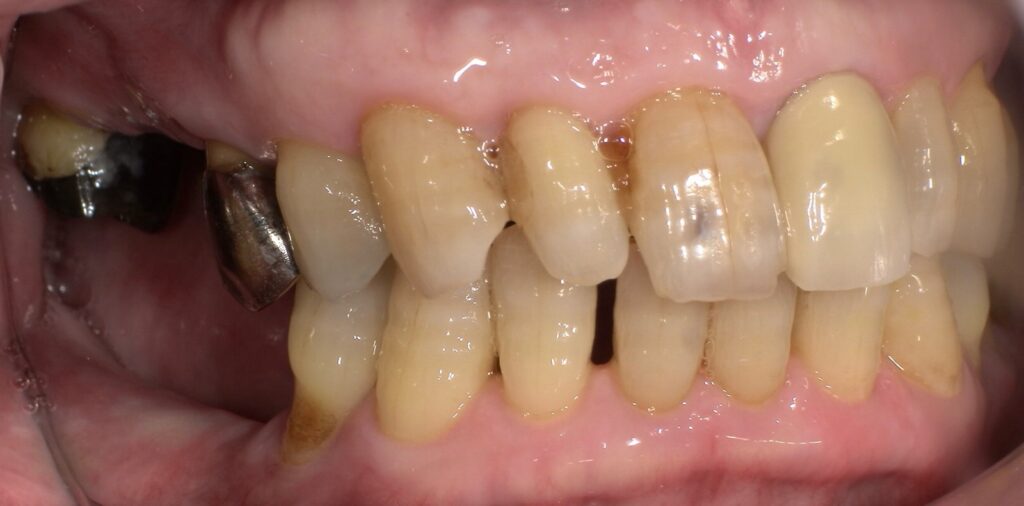

術前の側面からの写真です。